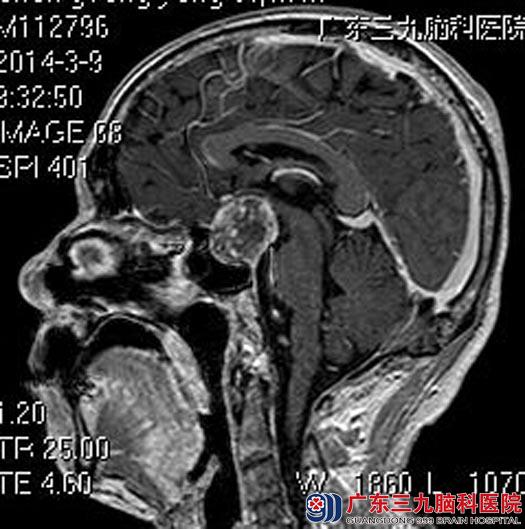

家属联系到广东三九脑科医院垂体瘤诊疗中心鲁明主任,建议进一步检查。头颅MR检查提示:鞍内及鞍上示一不规则信号影,大小约26.6mm×32.8mm×31.0mm,考虑垂体大腺瘤可能性大。

完善检查后,鲁明主任主刀,在全麻下行经鼻蝶垂体瘤切除术,术中在导航引导下建立路径,显微镜下见灰白色肿瘤涌出,期间夹带黑色血凝块,肿瘤质软,血供一般,予显微镜下切除肿瘤,术中对视神经保护完好,未见脑脊液漏。

手术前